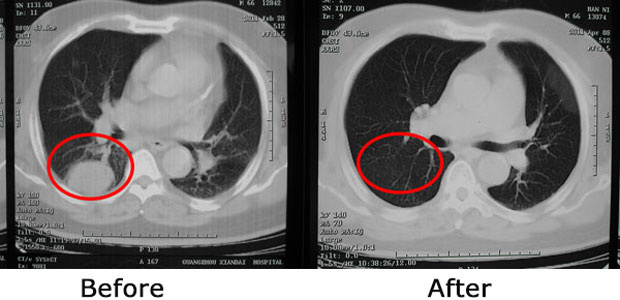

Minimally invasive therapy made 4.3 cm tumor in lung disappear

Early in 2011, I arrived at MCHG together with my family. Compared with oncology hospitals in Indonesia and Singapore, thorough tests and examinations were performed in MCHG . I was saddened that my tumor progressed from 3.6 cm to 4.3 cm. With my complicated chronic diseases, I lost my weight from 89kg down to 79kg. The Multidisciplinary Team (MDT) in MCHG immediately formulated an individualized minimally invasive treatment plan for me.

By interventional therapy, cryotherapy and particle implantation, I didn’t feel any side effects at all like those caused by radiotherapy and chemotherapy, instead, I was getting better each day. When I came to hospital for my 4th return visit in April 2011, CT showed that the 4.3 cm tumor in my lung had already disappeared. My weight also gradually returned back to normal. Apparently, my hair grew back and everything seemed fine as I was able to do more activities.